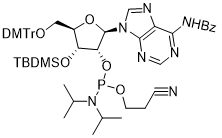

馬鞍山致研生物醫(yī)藥科技有限公司成立于馬鞍山市鄭浦港新區(qū)現(xiàn)代產(chǎn)業(yè)園。公司專(zhuān)注于生物小分子、醫(yī)藥中間體相關(guān)產(chǎn)品的研發(fā)和生產(chǎn),產(chǎn)品主要包括DNA亞磷酰胺單體、RNA亞磷酰胺單體、特殊單體以及按照客戶(hù)要求定制的RNA和DNA,并且公司提供定制合成等方面的研究服...

馬鞍山致研生物醫(yī)藥科技有限公司成立于馬鞍山市鄭浦港新區(qū)現(xiàn)代產(chǎn)業(yè)園。公司專(zhuān)注于生物小分子、醫(yī)藥中間體相關(guān)產(chǎn)品的研發(fā)和生產(chǎn),產(chǎn)品主要包括DNA亞磷酰胺單體、RNA亞磷酰胺單體、特殊單體以及按照客戶(hù)要求定制的RNA和DNA,并且公司提供定制合成等方面的研究服...